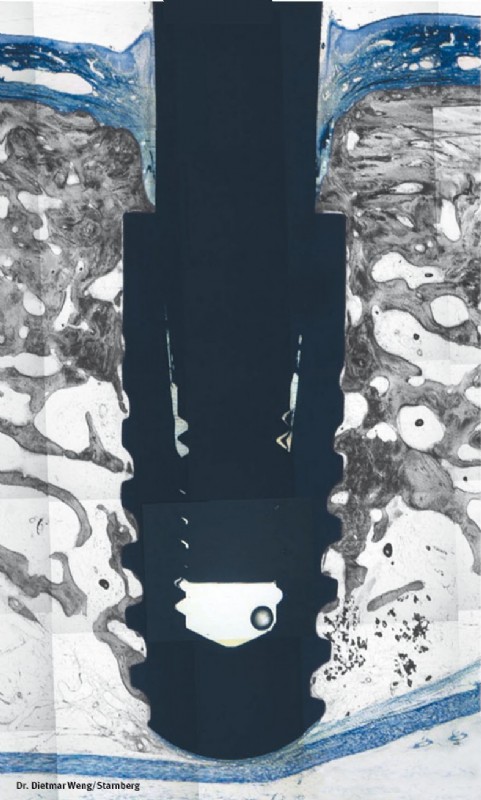

Hochqualitative künstliche Zahnwurzeln können natürliche Zähne sehr effektiv ersetzen. In einem ersten Schritt wird das Implantat-Bett aufbereitet, sodass das Implantat – eine Schraube aus Reintitan – problemlos in den Kiefer geschraubt werden kann. So können einzelne Zähne ersetzt oder Prothesen fixiert werden.